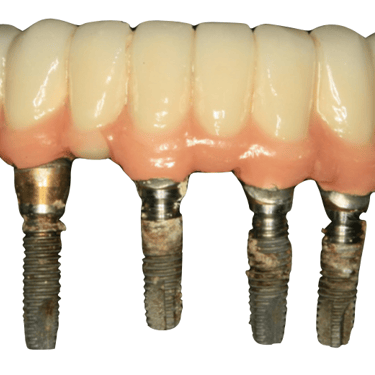

Edentulismo completo

El edentulismo completo es la ausencia total de dientes en una o ambas arcadas.

Los pacientes tienen dificultad para masticar, hablar y pueden sentirse incómodos con su apariencia.

El tratamiento puede incluir la colocación de una prótesis completa sobre implantes, proporcionando una solución fija y estable